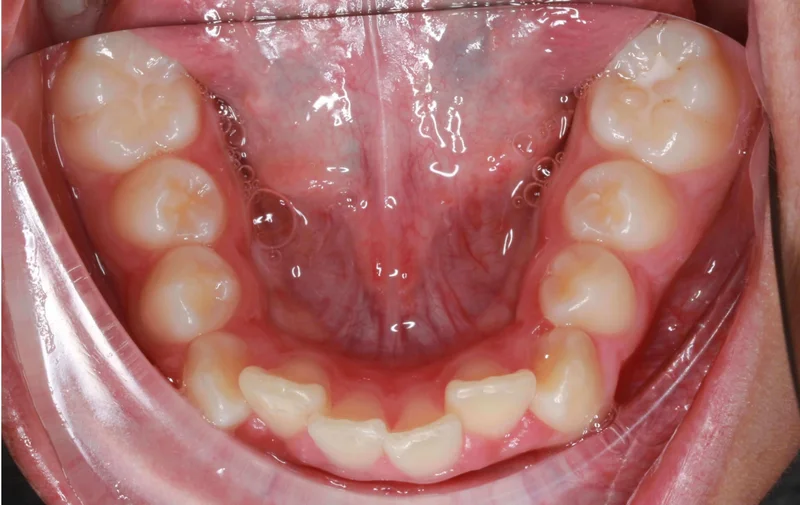

Lower Occlusal View

Lower Occlusal View - Before Treatment

Before